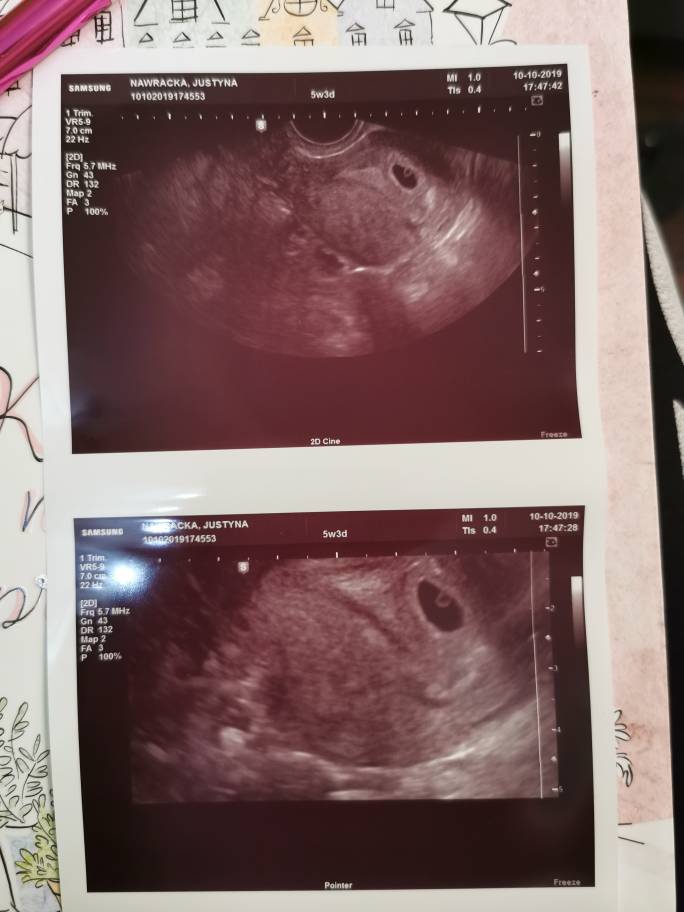

Zaczynam 5 tydzień... Ja wiem że to małe wartości... 1.10 miałam betę 22 a dziś, 10.10. beta 116.2 nie spodziewałam się że będzie tak mało... progesteron 38.22. Strasznie mi przykro... po tylu stratach i problemach... ostatnia miesiączka 07.09 (biochemiczna), cykle 26-30 dni.

• IMG_20191010_184023.jpeg

IMG_20191010_184023.jpeg

54,6 KB · Wyświetleń: 163